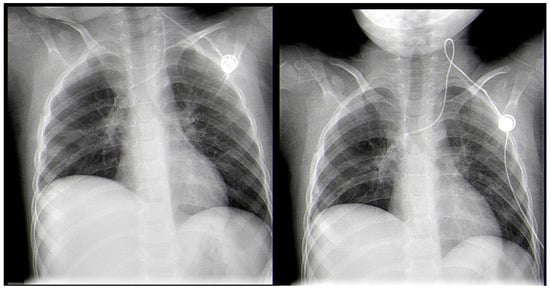

A Rare Case of Rhizomucor pusillus Infection in a 3-Year-Old Child with Acute Lymphoblastic Leukemia, Presenting with Lung and Brain Abscesses—Case Report

Invasive Mucormycosis (IM) is an extremely rare infection with a high mortality rate, caused by a group of fungi classified as Mucorales moulds. Rhizomucor pusillus is a saprophitic, thermophilic, and angioinvasive microorganism that grows and lives at about 45 °C and is usually found in different environmental spaces such as soil, air, water, food, and other organic matter. These features predispose the infection to wide dissemination, especially in immunocompromised patients and most often in children after chemotherapy for hematological malignancies (HMs). Mucormycosis in patients with hematologic malignancies and neutropenia represents between 0.07% and 4.29% of the concomitant diseases. IM can develop into an infection in different sites, but its most common manifestation is pulmonary, followed by rhino-orbital–cerebral and disseminated forms. In recent years, an increased morbidity rate has been associated with the ongoing COVID-19 pandemic, as cited in the literature. There are many publications with COVID-19-associated mucormycosis (CAM) cases. The present treatment protocol includes extensive and radical surgical debridement and systemic antifungal therapy with Liposomal Amphotericin B (L-AmB), Posaconazole, and Isavuconazole, either combined or as monotherapy. Despite these new treatment modalities, the mortality rate remains over 50%. We present a rare case of a 3-year-old child with acute lymphoblastic leukemia (ALL) and systemic Rhizomucor pusillus infection, diagnosed on the occasion of lung and brain abscesses. The patient underwent lung and brain surgery and is recovering well with no further complications. The two-year follow-up period shows no signs of recurrence of the disease. Full article

Show Figures

Figure 1